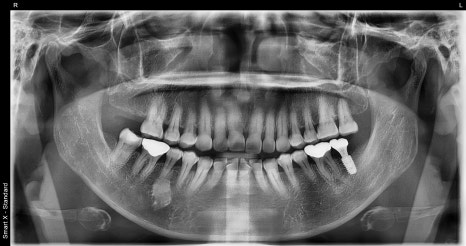

A patient in their 50s who visited with a molar issue

This patient came in for scaling

and during the visit, the condition of the molar was checked.

There had been a prosthetic restoration on the existing molar, but the prognosis was poor,

so extraction was ultimately necessary.

Treatment that also considers adjacent teeth

In this case,

in addition to the implant, crown treatment on the adjacent tooth

was also performed.

An implant is not a stand-alone treatment;

it is important to maintain balance with the surrounding teeth.